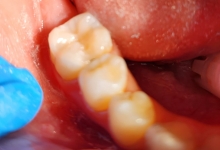

Clinica LUY ESTHETIC ART defineste parodontoza ca fiind rezultatul direct al placii dentare, care se depune pe suprafata dintilor, dar si in apropiere de marginea gingivala. Aceasta boala duce la pierderea dintilor, chiar daca ei sunt aparent sanatosi si nu prezinta carii. Edentatiile, afecteaza vorbirea, aspectul, dar si capacitatea de a mesteca.

Boala parodontala are un caracter progresiv. Pentru cazurile mai grave, recomandam tratamentul parodontal chirurgical rezectiv sau regenerativ.

– mobilitatea sau deplasarea dintilor;

– retractii gingivale cu expunerea radacinilor dentare;